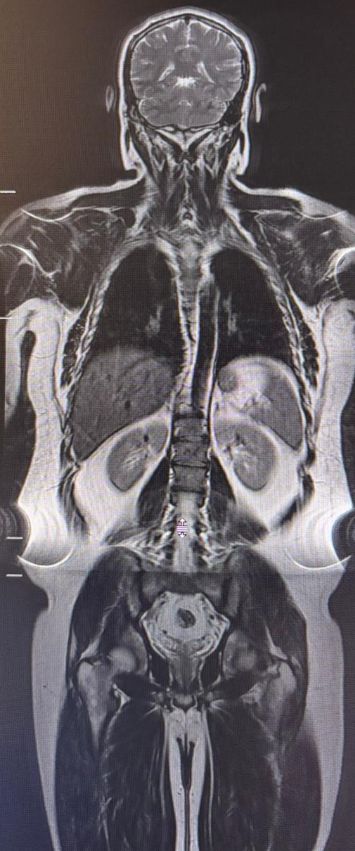

Ressonância magnética de corpo inteiro

A ressonância magnética de corpo inteiro (RM de corpo inteiro, ou WB-MRI) se consolidou como uma das ferramentas mais relevantes da imagem oncológica moderna. Trata-se de um método sem radiação ionizante, com excelente contraste tecidual e grande sensibilidade para detectar doença em múltiplos segmentos do corpo. No entanto, embora o nome do exame seja o mesmo, seu papel muda de forma importante conforme a indicação clínica. Isso fica especialmente claro quando comparamos sua aplicação na hematologia, particularmente no mieloma múltiplo, com seu uso na oncologia de vigilância, como no rastreio de pacientes com síndrome de Li-Fraumeni.

Essa diferença de finalidade muda tudo: muda o protocolo, muda o peso das sequências e muda a forma como o radiologista lê o exame. No mieloma, a pergunta principal é: há infiltração medular? Quantas lesões existem? Há resposta ao tratamento? No Li-Fraumeni, a pergunta é outra: há alguma massa suspeita em qualquer parte do corpo? Em um cenário, o exame é medula-centrado; no outro, ele é rastreamento-centrado.

Essas diferenças mostram que a RM de corpo inteiro não deve ser vista como um exame único e genérico. Ela é, na verdade, uma plataforma de imagem extremamente versátil, cujo verdadeiro valor depende da indicação correta, do protocolo adequado e da pergunta clínica bem definida. No mieloma, a prioridade é compreender a distribuição e a atividade da doença medular. No Li-Fraumeni, a missão é procurar precocemente um tumor potencialmente silencioso em qualquer parte do corpo.

A RM de corpo inteiro ocupa hoje um espaço de destaque tanto na hematologia quanto na oncologia, mas por razões diferentes. No mieloma múltiplo, ela é uma ferramenta refinada para diagnóstico e monitoramento da doença óssea e medular. Na oncologia hereditária, como na síndrome de Li-Fraumeni, ela assume um papel de vigilância ampla, buscando antecipar o diagnóstico de tumores potencialmente agressivos. Entender essa diferença é essencial para protocolar melhor, interpretar com mais precisão e oferecer ao paciente o exame certo, com a estratégia certa.